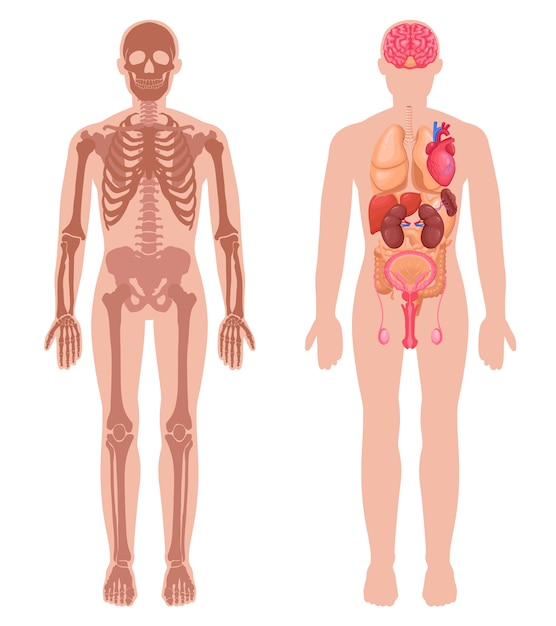

Human Anatomy Set 6168563

14/11/2025

ร่างกายมนุษย์